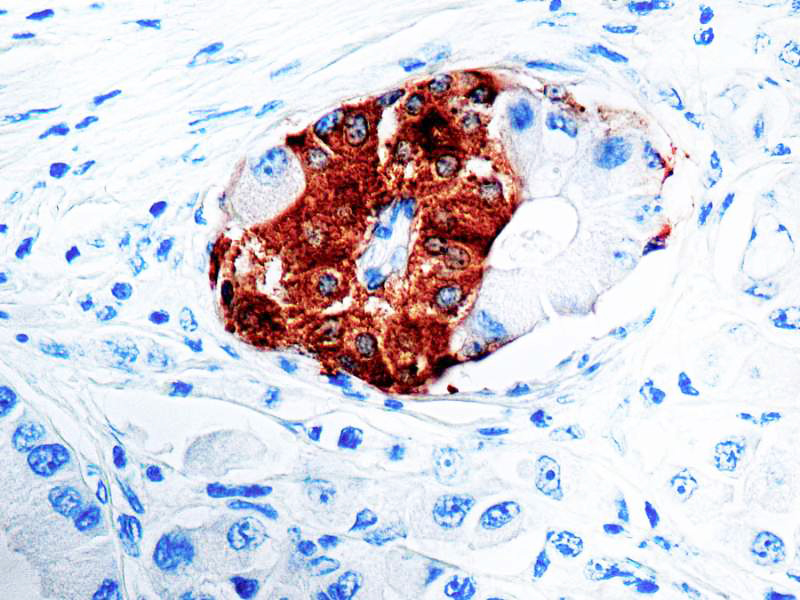

Synaptophysin (SYP02)

This antibody isspecific to a 38 kDa protein. Synaptophysin is an glycoprotein occurring in presynaptic vesicles of neurons in the brain, spinal cord, retina, vesicles of adrenal medulla and in neuromuscular junctions. This antibody reacts with neuroendocrine neoplasms of neural as well as epithelial types.

| Cellular Localization | Cytoplasmic |

| Positive Control Tissue | Pancreas |